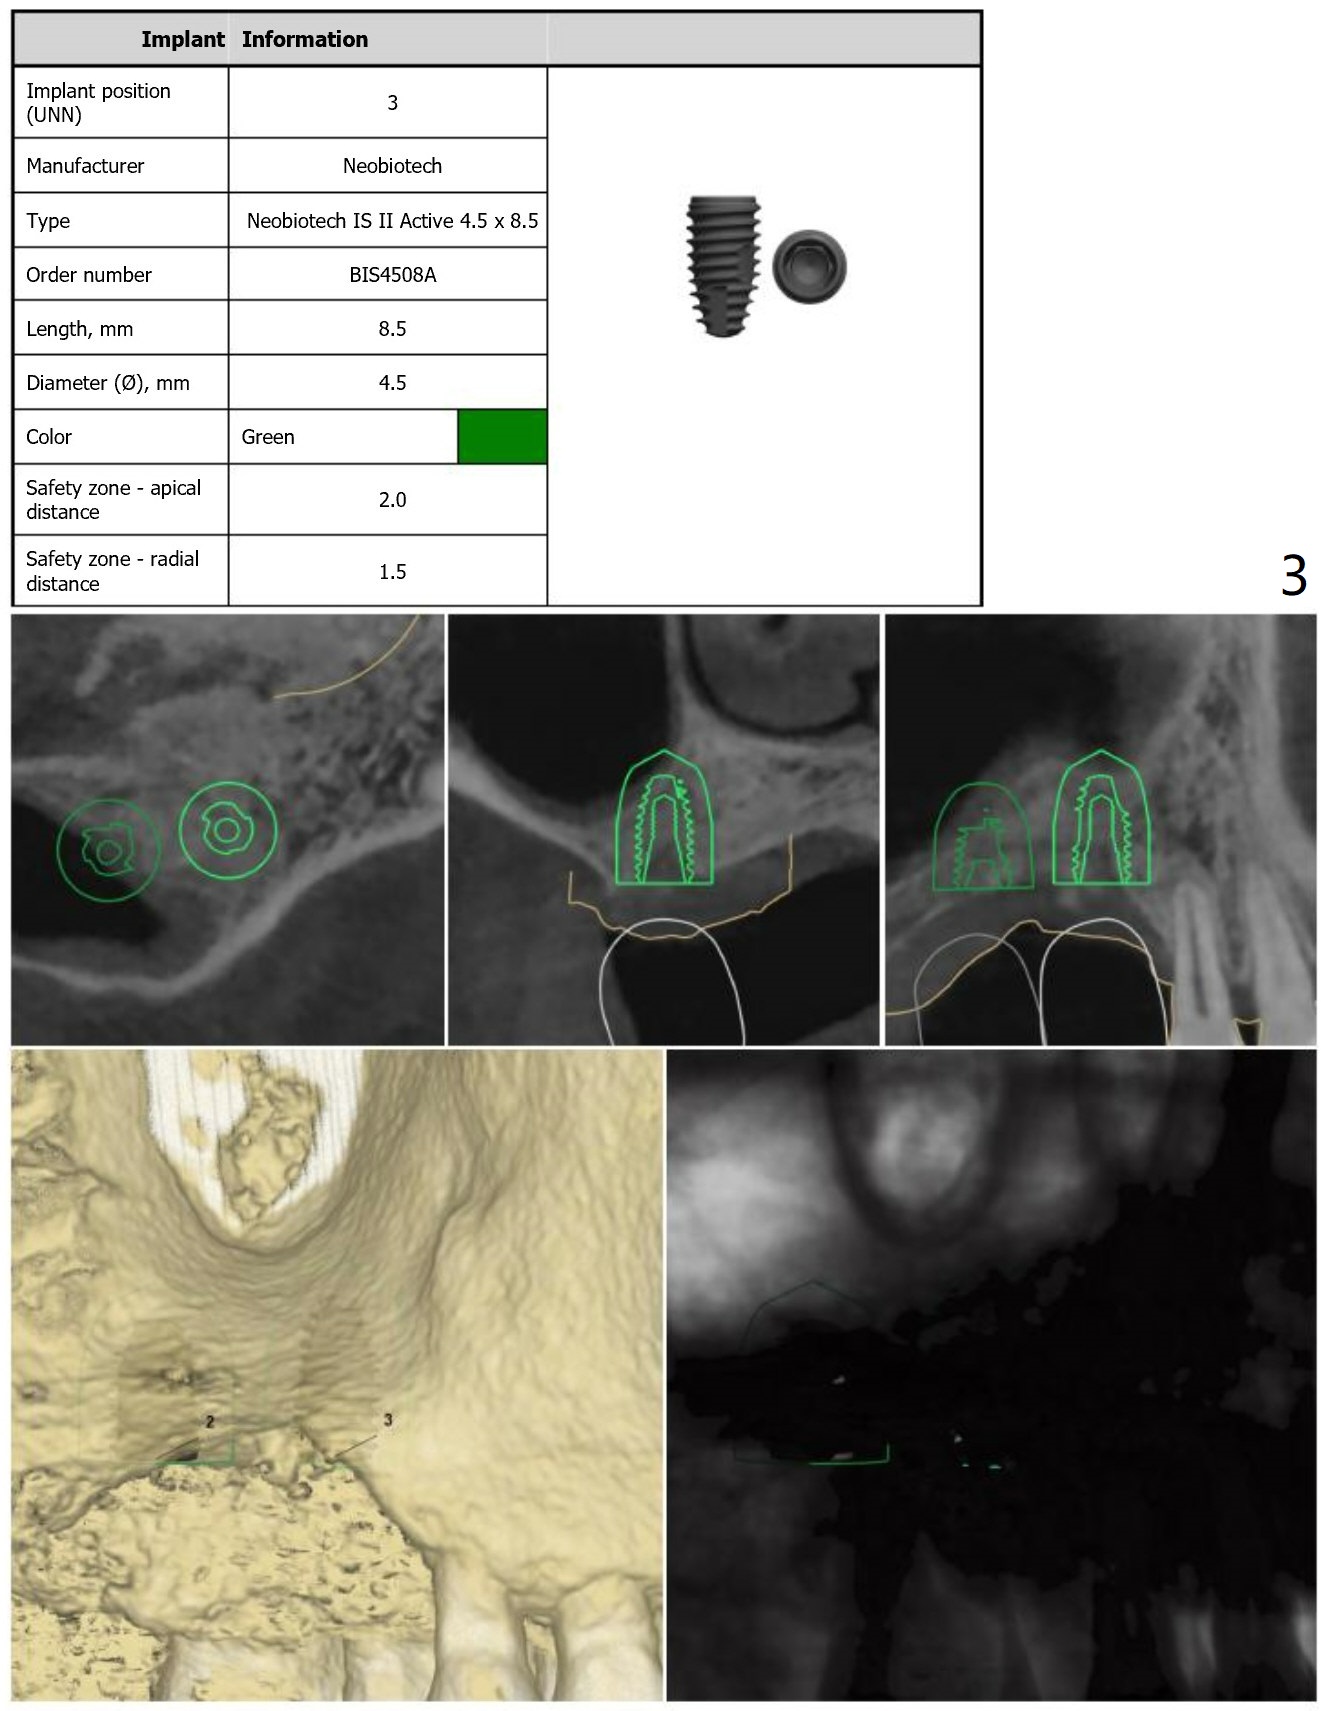

Short and Hard Bone

Return to Upper Molar Immediate Implant, Trajectory